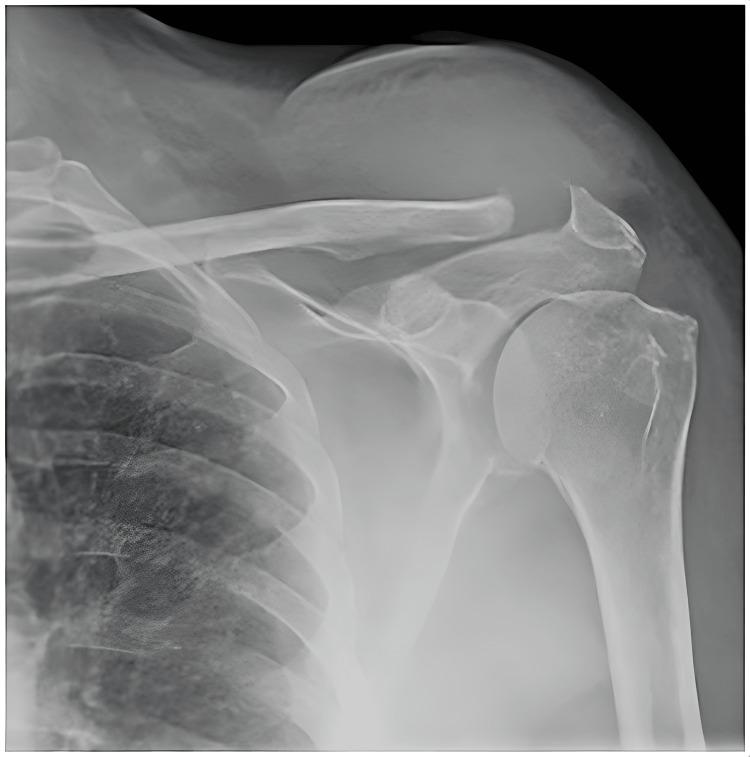

A 60-year-old diabetic patient presented with acute pain and swelling localized to the left acromioclavicular joint. Laboratory and radiological investigations revealed the presence of pus in the left acromioclavicular joint along with bony erosion of the lateral end of the left clavicle. She was treated with open arthrotomy, debridement, and appropriate antibiotics for the causative methicillin-resistant Staphylococcus aureus (MRSA) infection. Prompt diagnosis and timely intervention can reduce the morbidity and mortality due to septic arthritis. We conducted a review of the literature on patients treated for isolated septic arthritis of the acromioclavicular joint.

摘要

一名60岁的糖尿病患者出现左肩锁关节局部急性疼痛和肿胀。实验室和影像学检查显示左肩锁关节有脓液,同时左锁骨外侧端有骨质侵蚀。她接受了切开手术、清创术,并使用了针对致病性耐甲氧西林金黄色葡萄球菌(MRSA)感染的适当抗生素进行治疗。及时诊断和适时干预可降低化脓性关节炎导致的发病率和死亡率。我们对治疗肩锁关节孤立性化脓性关节炎患者的文献进行了综述。